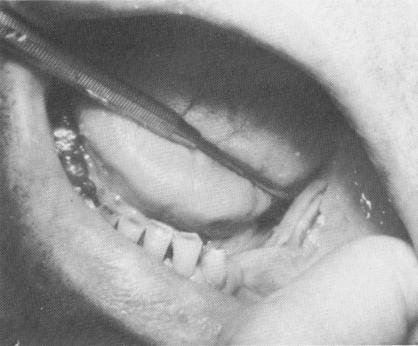

Fig. 11-35. Groove made at implant site.

Fig. 11-36. Implant set in groove.

1 Groove made at mandibular implant site for bladevent

2 Bladevent set in prepared mandibular groove